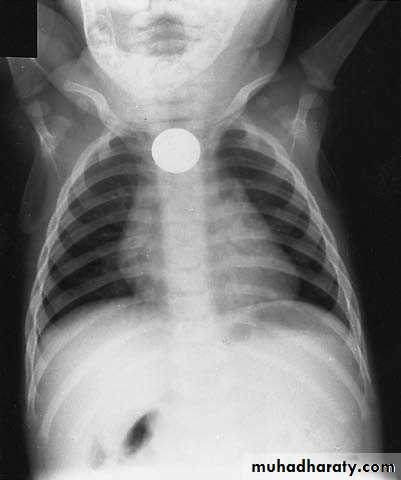

Esophageal F.B

Clinically:salivation +no strioder1st F.b in Lt main bronchus removed by bronchoscopy